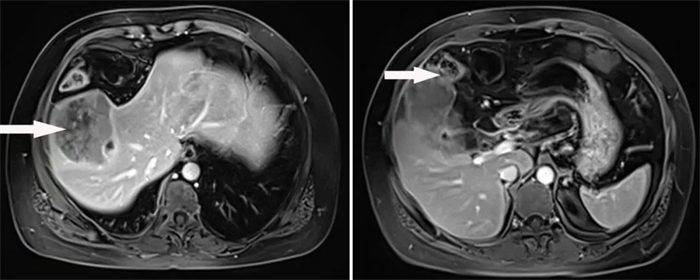

患者3,55岁女性,因“上腹部疼痛1周”入院,经MRI检查提示肝内占位性病变,累及胆囊、横结肠,考虑肝恶性肿瘤。